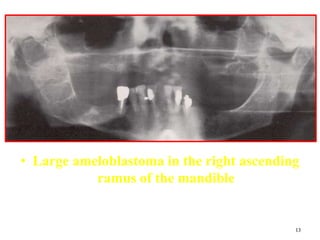

• Large ameloblastoma in the right ascending

ramus of the mandible